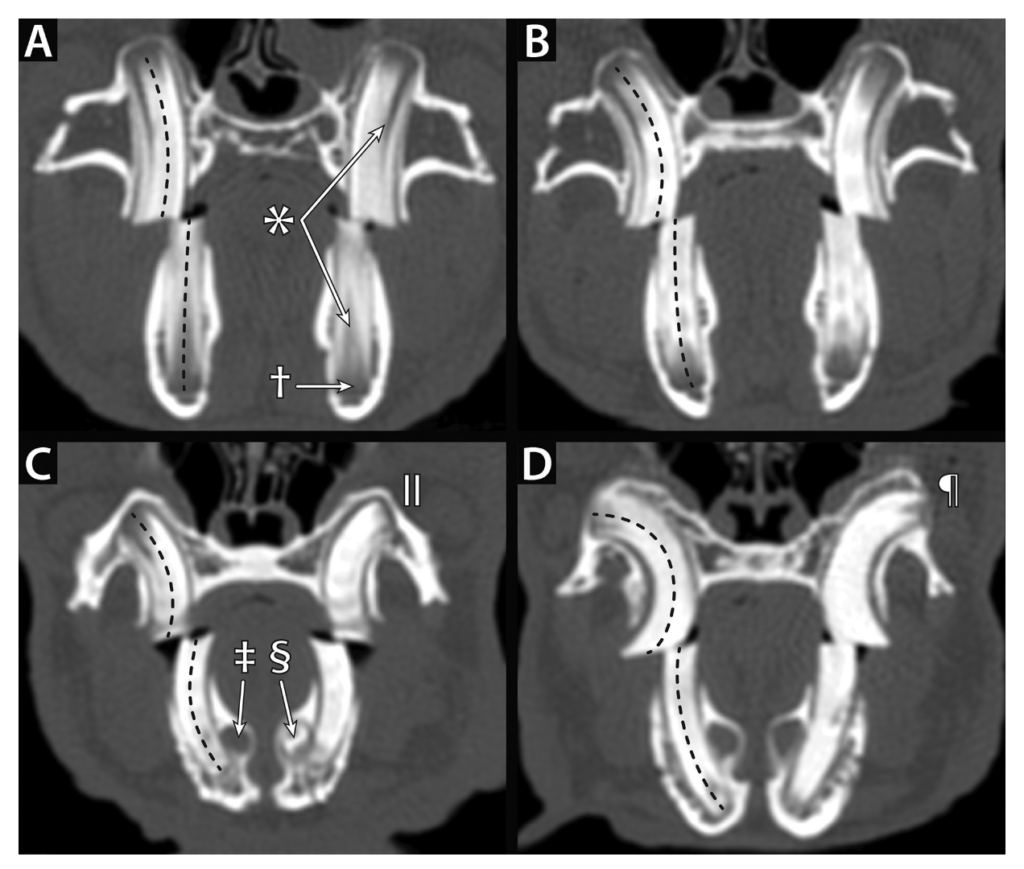

「Computed tomographic findings of dental disease in domestic rabbits (Oryctolagus cuniculus): 100 cases (2009–2017)」より引用。

ウサギの小臼歯および大臼歯の横断面CT画像。

A正常

B軽度湾曲

C中等度の湾曲

D著しい湾曲